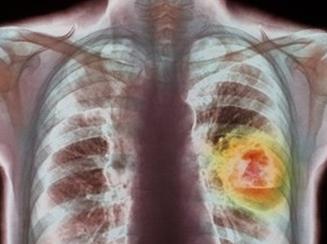

암의 원인과 이유중 다양한 요인중 장내세균에 관심을 갖을 필요가 있다.

유해형 부패로 유인하는 유인균은 섭취된 음식에서 니트로소아민등 400가지 이상의 독소가 암을 제거하는 명령물질 사이토카인을

교란하여 암 세포를 제거하지 못해 암 덩어리로 발전한다.